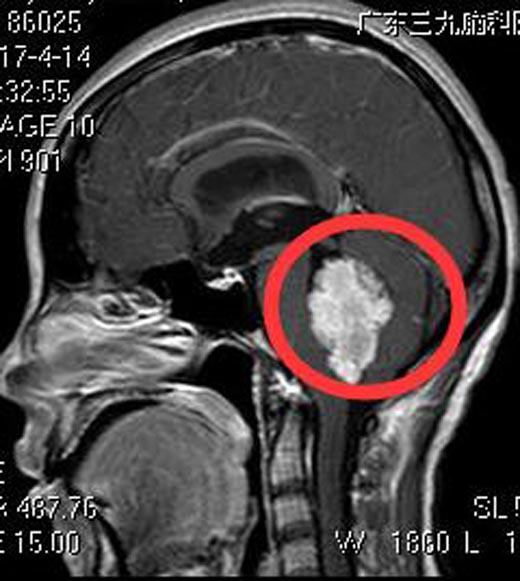

为明确原因,在当地医院行头颅CT检查,提示:四脑室占位,并梗阻性脑积水。急诊行脑室外引流,术后转入广东三九脑科医院神经外五科。头颅MR检查提示:四脑室巨大占位性病变,大小约3.8cm×4.8cm×3.3cm,考虑为室管膜瘤可能性大。